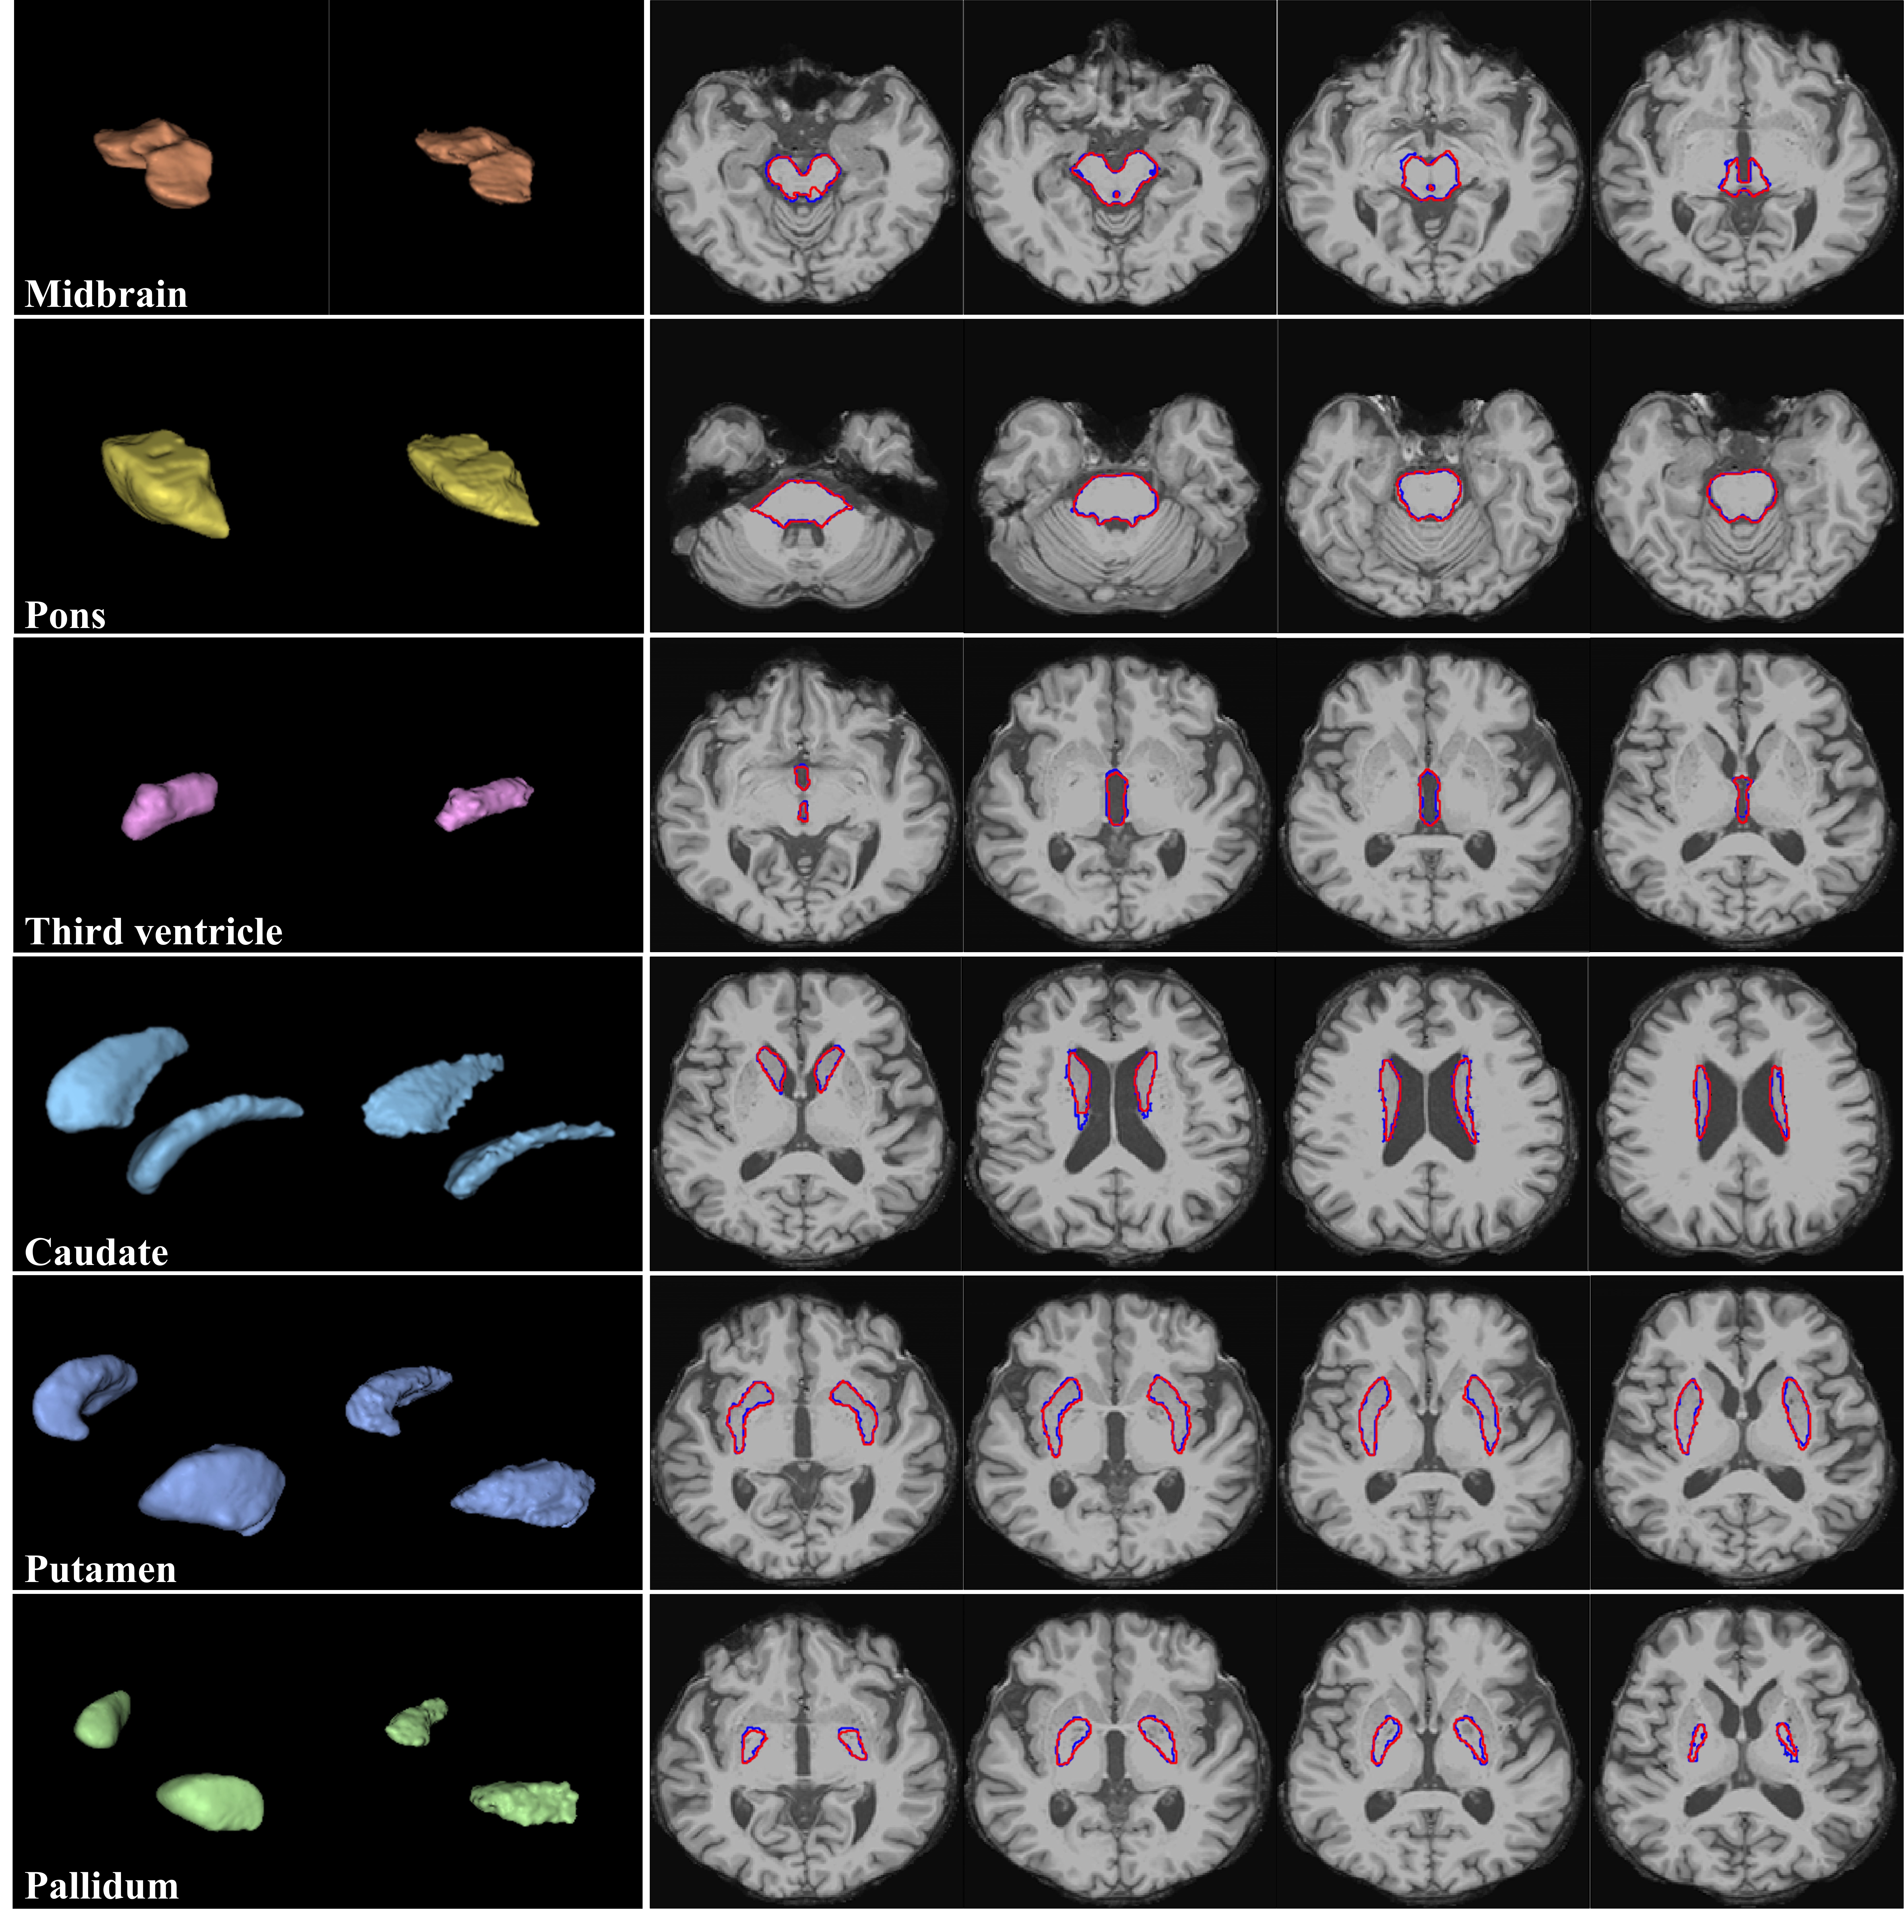

Figure 4: Segmentation results of CNN-based V-Net (left 3D images in first column and red-highlighted areas in second column) and FS (right 3D images in first column and blue-highlighted areas in second column) for each brain structure.

Refer to caption

Figure 5: Segmentation results of ViT-based UNETR (left 3D images in first column and red-highlighted areas in second column) and FS (right 3D images in first column and blue-highlighted areas in second column) for each brain structure.

Table 2 lists the time required to segment the six brain structures per patient. As mentioned in Section 2.2.2, the brain structure segmentation using FS sequentially processes the remaining of the recon-all pipeline and the complete brainstem substructure pipeline. In FS segmentation, we removed the analysis time of preprocessing (i.e., time to extract the skull-stripped image from the original MRI) described in Section 2.2.2. The resulting time provides a fair comparison of the total times, as FS and DL models use the skull-striped MRI scan as input to derive the final segmentation results, indicated by bold values in Table 2.

Segmentation and prediction results of V-Net and FS are illustrated in Figure 4. The corresponding results of UNETR are illustrated in Figure 5. The Dice score was obtained (Table 3) to evaluate the performance of 3D image segmentation. The CNN- and ViT-based models showed high Dice scores above 0.85 for all the brain structures. The Dice scores were higher for the midbrain and pons than for the basal ganglia (i.e., caudate, putamen, pallidum), possibly because the brainstems are surrounded by cerebrospinal fluid and provide a stronger contrast for accurate segmentation. The ViT-based model showed a higher Dice score than the CNN-based model, which in turn showed a much shorter segmentation time than the ViT-based model (e.g., 3.48 s for V-Net and 48.14 s for UNETR, as shown in Table 2)999Although we evaluated V-Net and UNETR in different development environments of TensorFlow and PyTorch, respectively, we expect the CNN-based V-Net to be competitive in speed with the ViT-based UNETR given the segmentation speed difference of at least 10 times in our experiments. In addition, the CNN-based V-Net had a similar performance to the ViT-based UNETR in actual disease classification, as listed in Table 4.